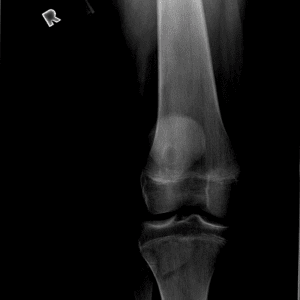

Pediatric Radiographs